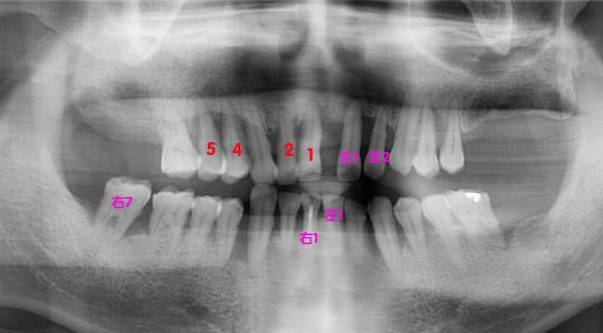

【byb.cn 大道至簡】2015年1月10日,我同時拔掉了4顆牙,即右上1、2、4、5顆牙,保留了3、6;與此同時,我還將在1月14日,繼續(xù)拔4顆牙,即左上1、2,左下1、右下1和右下7。換言之,在4天之內(nèi),我要拔掉9顆牙。

紅色的,是在1月10日拔掉的牙,粉色的,是即將在1月14日拔掉的牙